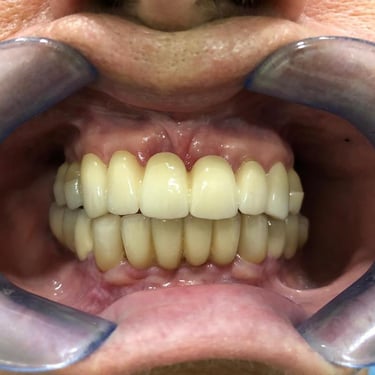

NUESTROS CASOS REALES